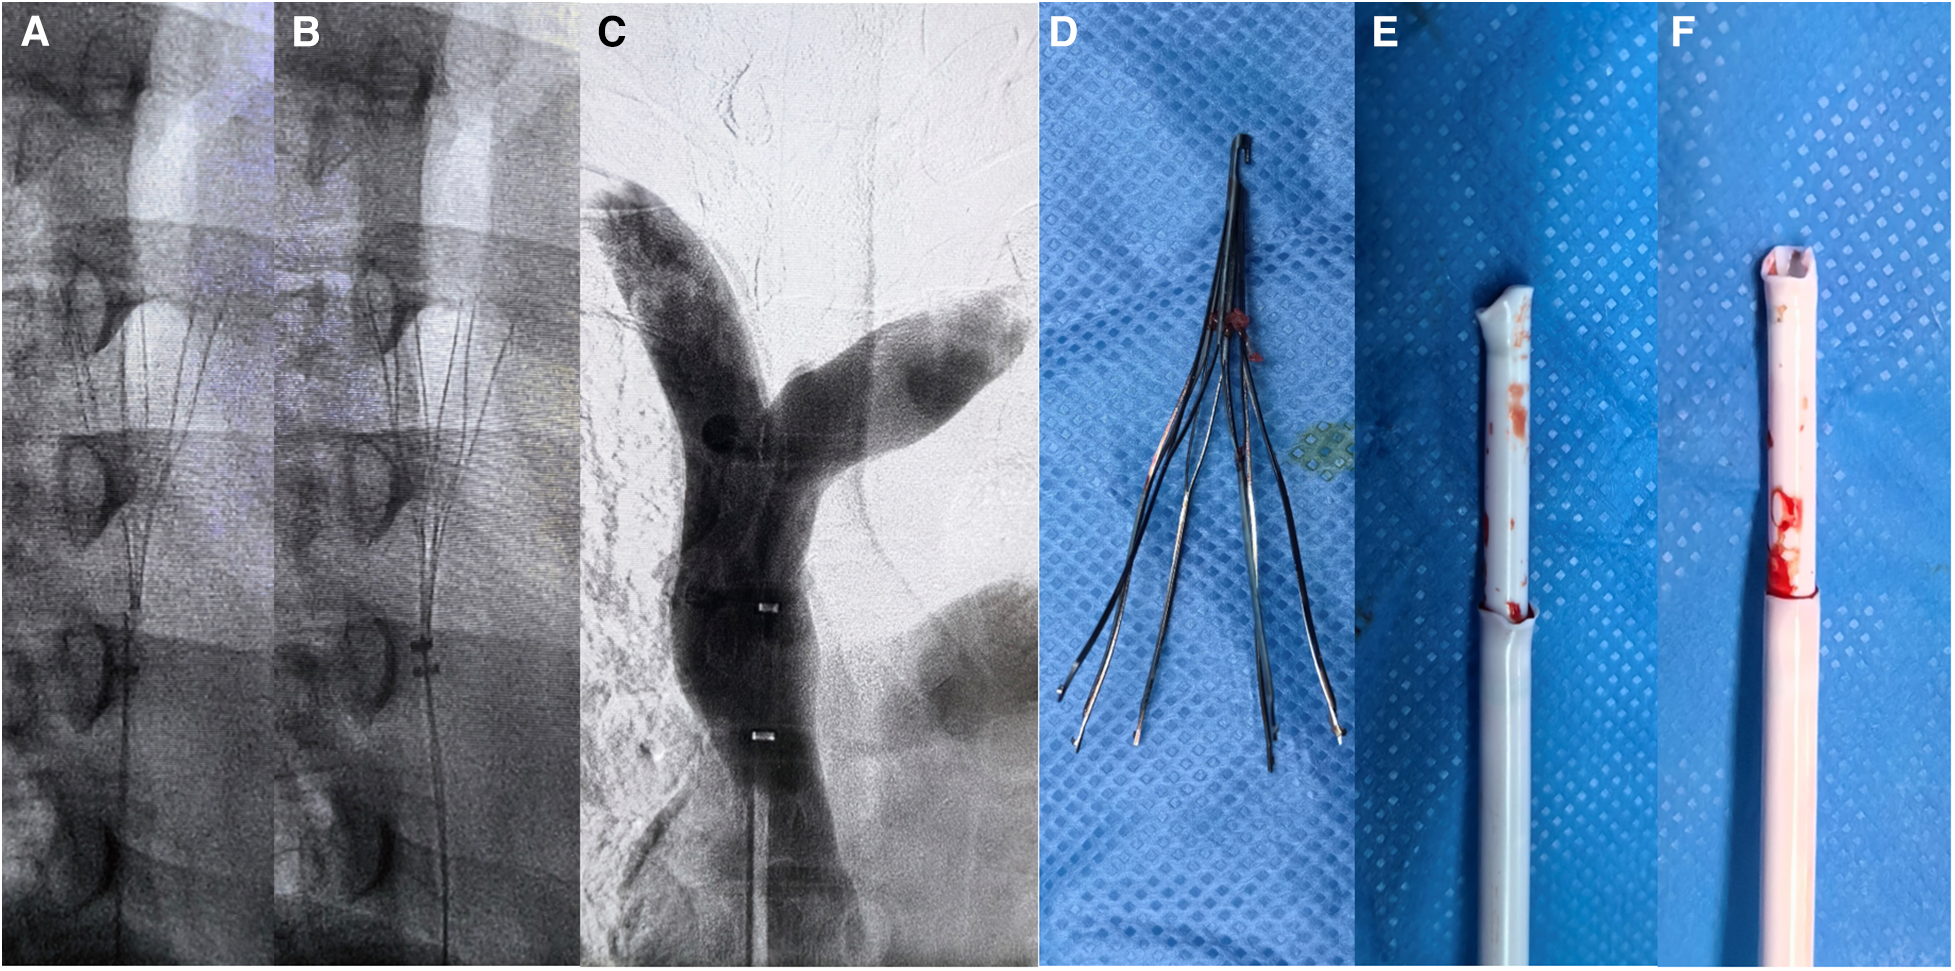

Angiographic imaging of the right common femoral vein showed that the inferior vena cava was unobstructed and no thrombus observed. Repeated multiangle angiography showed that the filter retraction hook had possibly entered the SVC wall (Figures 2A,B). ZYLOX filter retrieval kit was introduced but difficulties were encountered when attempting to capture the filter retraction hook. To solve this issue, we utilized a modified loop-snare technique (13) by introducing a pigtail catheter and a hydrophilic guidewire (Figure 2E). The pigtail catheter had its tip partially cut (Figures 2C,D) and was rotated to be guided into the interspace between the filter and the SVC wall (Figure 2B, red arrows). The guidewire was used to increase the catheter support and was advanced to free its end to be snared and externalized. A wire loop was formed across the proliferative tissue and was used to cut and destroy the proliferative tissue surrounding the retraction hook through the exertion of counteracting forces by the guidewire and retrieval sheath (Figures 3A,B), and the filter was successfully removed by directly suspension of the guidewire. It is worth noting that the patient experienced uncomfortable symptoms such as chest pain and palpitations during the removal process, but these symptoms disappeared once the operation was successfully completed. Repeated multiangle angiography showed no contrast medium spillage (Figure 3C). Finally, the filter was removed successfully and completely (Figure 3D). We also observed that the tip of the retrieval sheath was significantly deformed (Figures 3E,F).

Figure 2

Images of the loop-snare technique steps. (A,B) Multiangle angiography of the superior vena cava. Red arrows marked the interspace between the filter and the SVC wall where the wire loop was formed. (C,D) The pigtail catheter shape with its tip partly cut. (E) Modified loop-snare technique using a decapitated pigtail catheter.

Figure 3

Filter removal process images. (A,B) Modified loop-snare technique for cutting the proliferated tissue around the retraction hook, with the guidewire directly suspending the retraction hook. (C,D) After the filter was successfully removed, no damage to the superior vena cava was observed by contrast imaging, and the filter was completely removed. (E,F) The deformed shape of the filter retrieval devices.